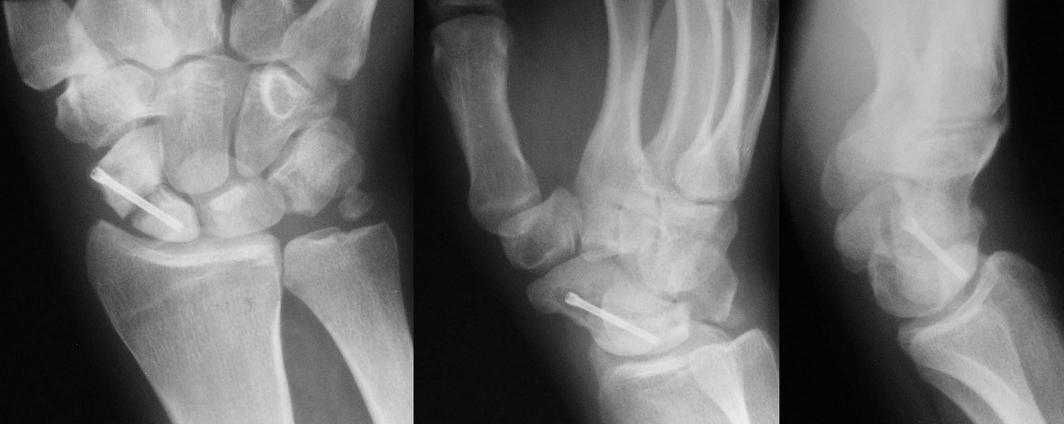

Мужчина 26 лет, профессиональный мотогонщик, во время показательных

выступлений упал с мотоцикла. Поступил на третьи сутки после травмы с

диагнозом: чрезладьевидно-перилунарный вывих правой кисти, перелом

шиловидного отростка правой локтевой кости. При поступлении закрытое

ручное вправление вывиха, гипсовая фиксация. На десятые сутки после

травмы выполнена операция: открытый остеосинтез ладьевидной кости

компрессирующим винтом Autofix от Small Bones Innovations. Состояние

спустя пять месяцев после операции представлено на иллюстрациях,

беспокоят боль и ограничение движений в лучезапястном суставе.

Man 26 years old, professional motorcycle racer during show fell down

the motorcycle. In three days transscaphoperilunate dislocation of

the right hand with fracture of ulna styloid process were diagnosed,

closed reduction and cast fixation were performed. In ten days open

osteosynthesis of navicular bone with compression screw AutoFix by

Small Bones Innovations was carried out. Status in five and a half

monthes after operation is presented on the illustrations.

Patient complains of pain and motion deficiency in wrist joint.